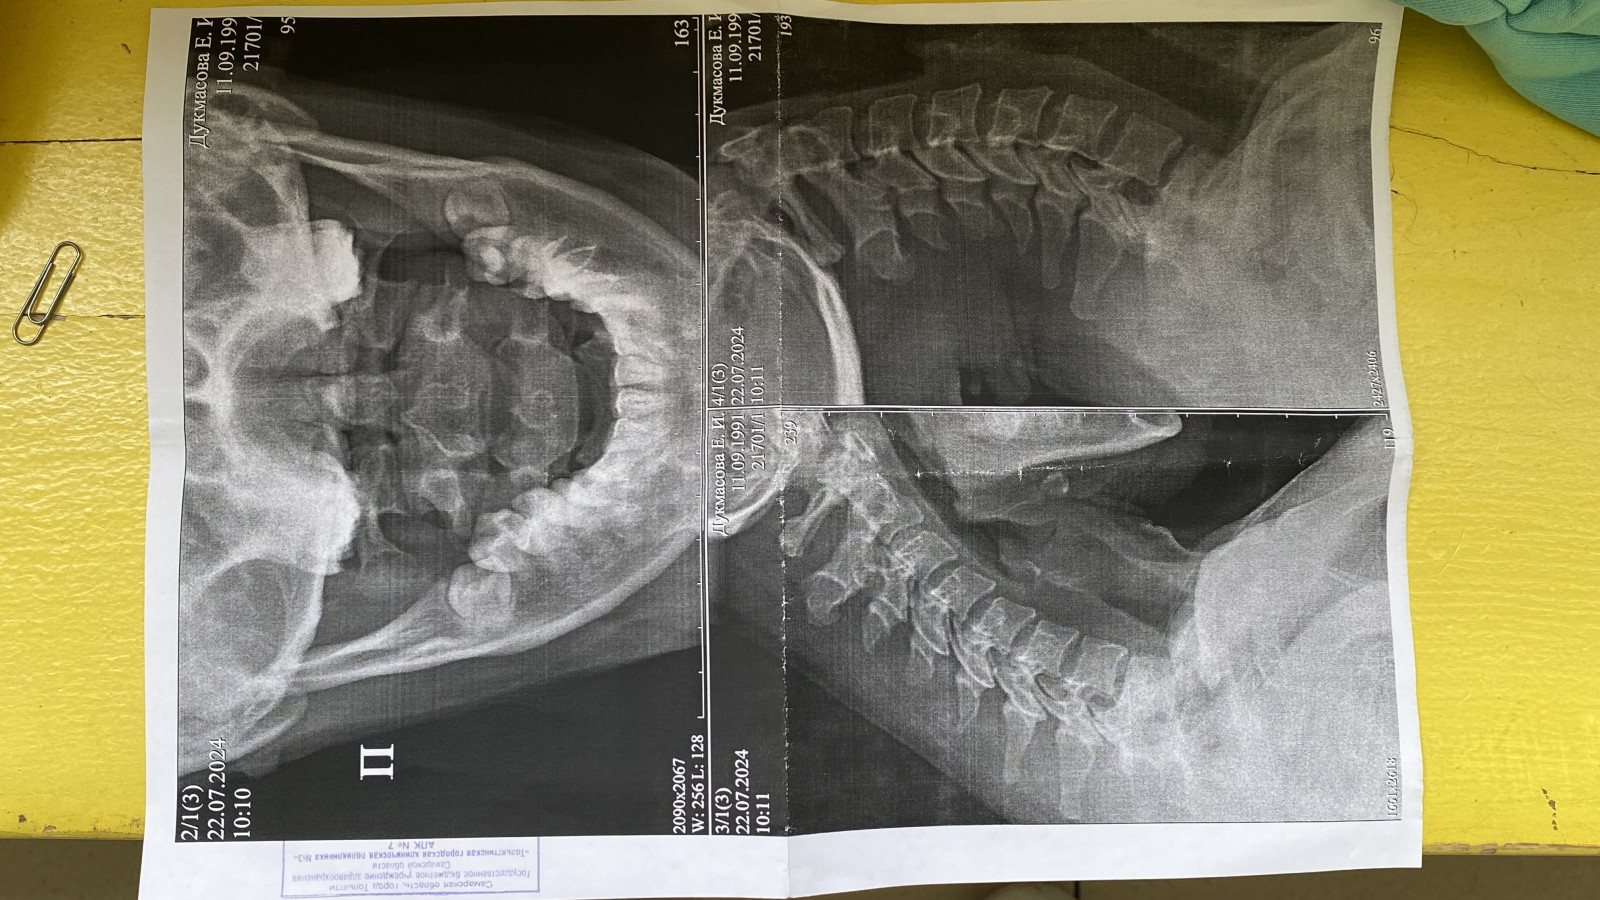

Рентгеновские технологии: усиленные экраны 35x35